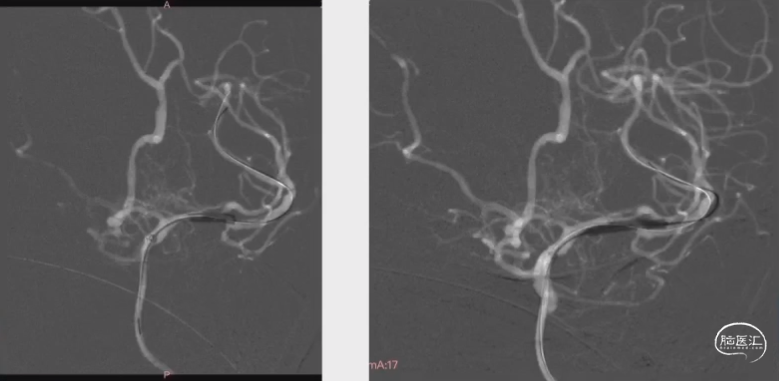

术后3月经桡动脉入路DSA复查